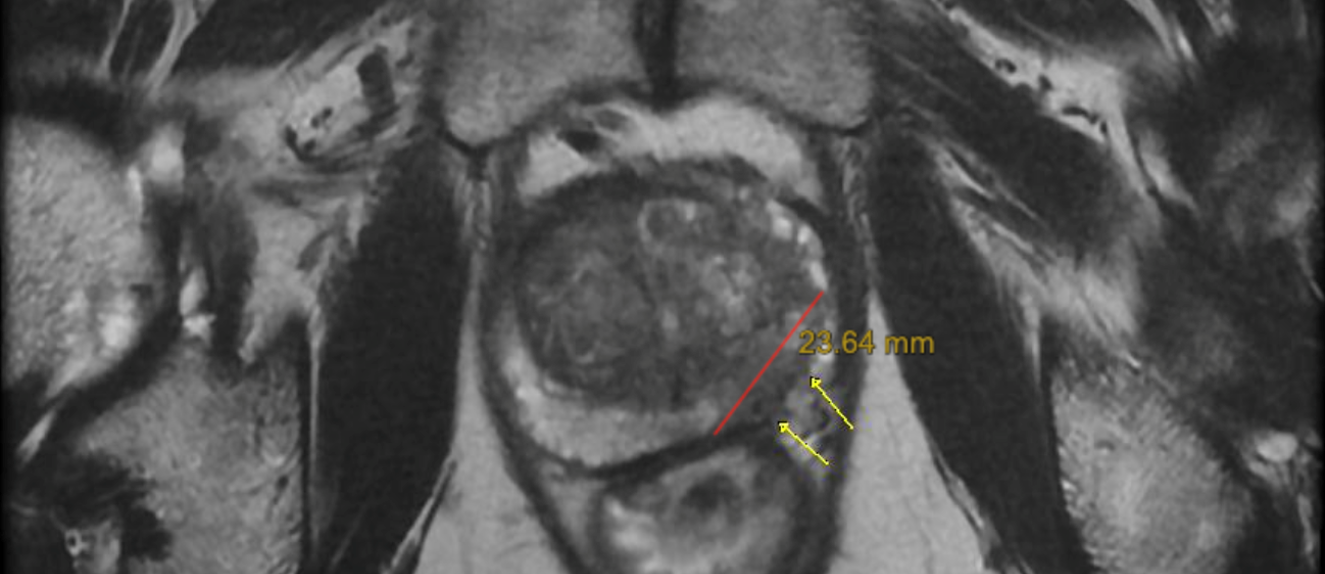

• RNMmp

– Nódulo 2,4cm (PI-RADS 5), pequena EEC e invasão de FVN esquerdo